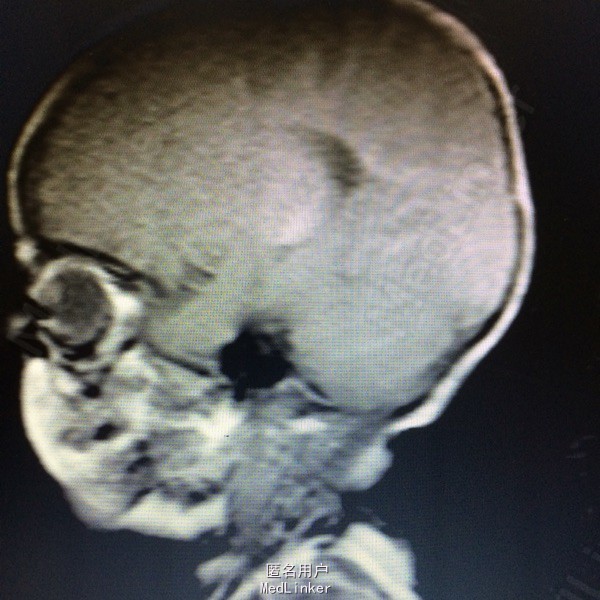

主诉:发现枕部肿块7个月 病史:患儿7月男婴,出生后即被家人发现枕后部肿物,大小约1cm*1cm*1cm,边界清楚,质软,表面光滑,挤压时患儿无哭闹等。

查体:枕后部肿物 辅助检查:行头颅MR提示顶针部中线异常信号,多考虑脑膜膨出

诊断:脑脊膜膨出 处理:枕部脑膜膨出囊切除术➕硬脑膜修补术